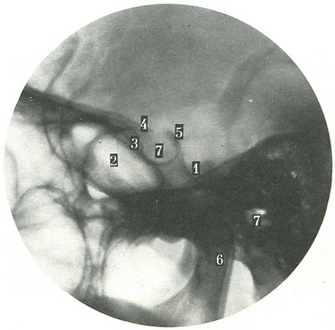

Для детального вивчення турецького сідла виконують прицільний знімок з відстані 60 див. На знімку разом з турецьким сідлом повинні бути малі крила, воздухоносная пазуха клиноподібної кістки і скат (рис. 67).

67. Бічна прицільна рентгенограма турецького сідла (по Л. Д. Линденбратену). 1 - майданчик клиноподібної кістки; 2 - пазуха клиноподібної кістки; 3 - горбок сідла; 4 - апофіз нахиленого відростка; 5 - апофіз заднього нахиленого відростка; 6 - спинка турецького сідла; 7 - дно турецького сідла. |